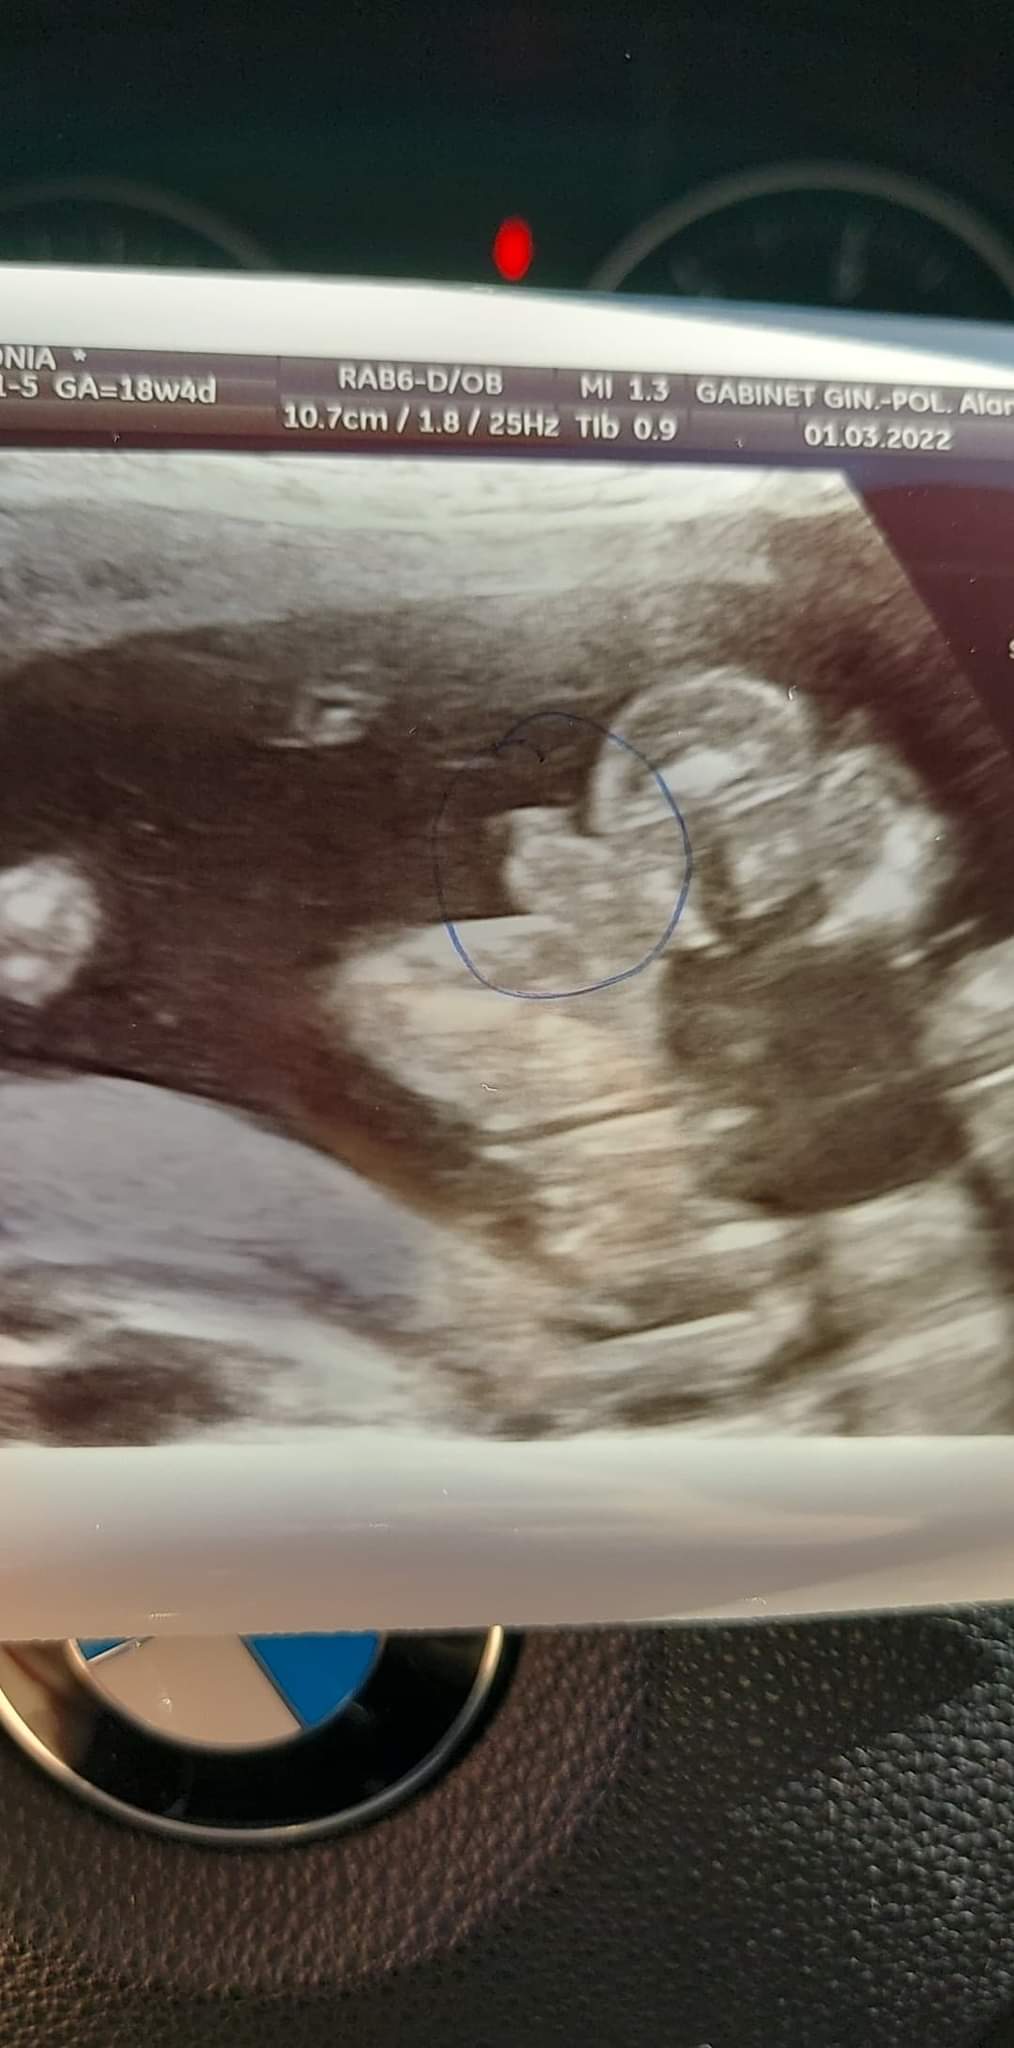

Jestem w 18+4 zdj robione dzis przez lekarza, który także stwierdził chłopca, chociaż ostatnio była niby dziewczynka. I to on zaznaczył, że to niby jądra a to co odstaje to prącie.@Sonia1723 To co zaznaczyłaś jest moim zdaniem od dupy strony. Ja nie podejmę się interpretacji. A który masz tc? Bo moim zdaniem z tego zdjęcia nie da się płci odczytać, a to co zaznaczyłaś to może być pępowina, która zasłania to co istotne ;-)